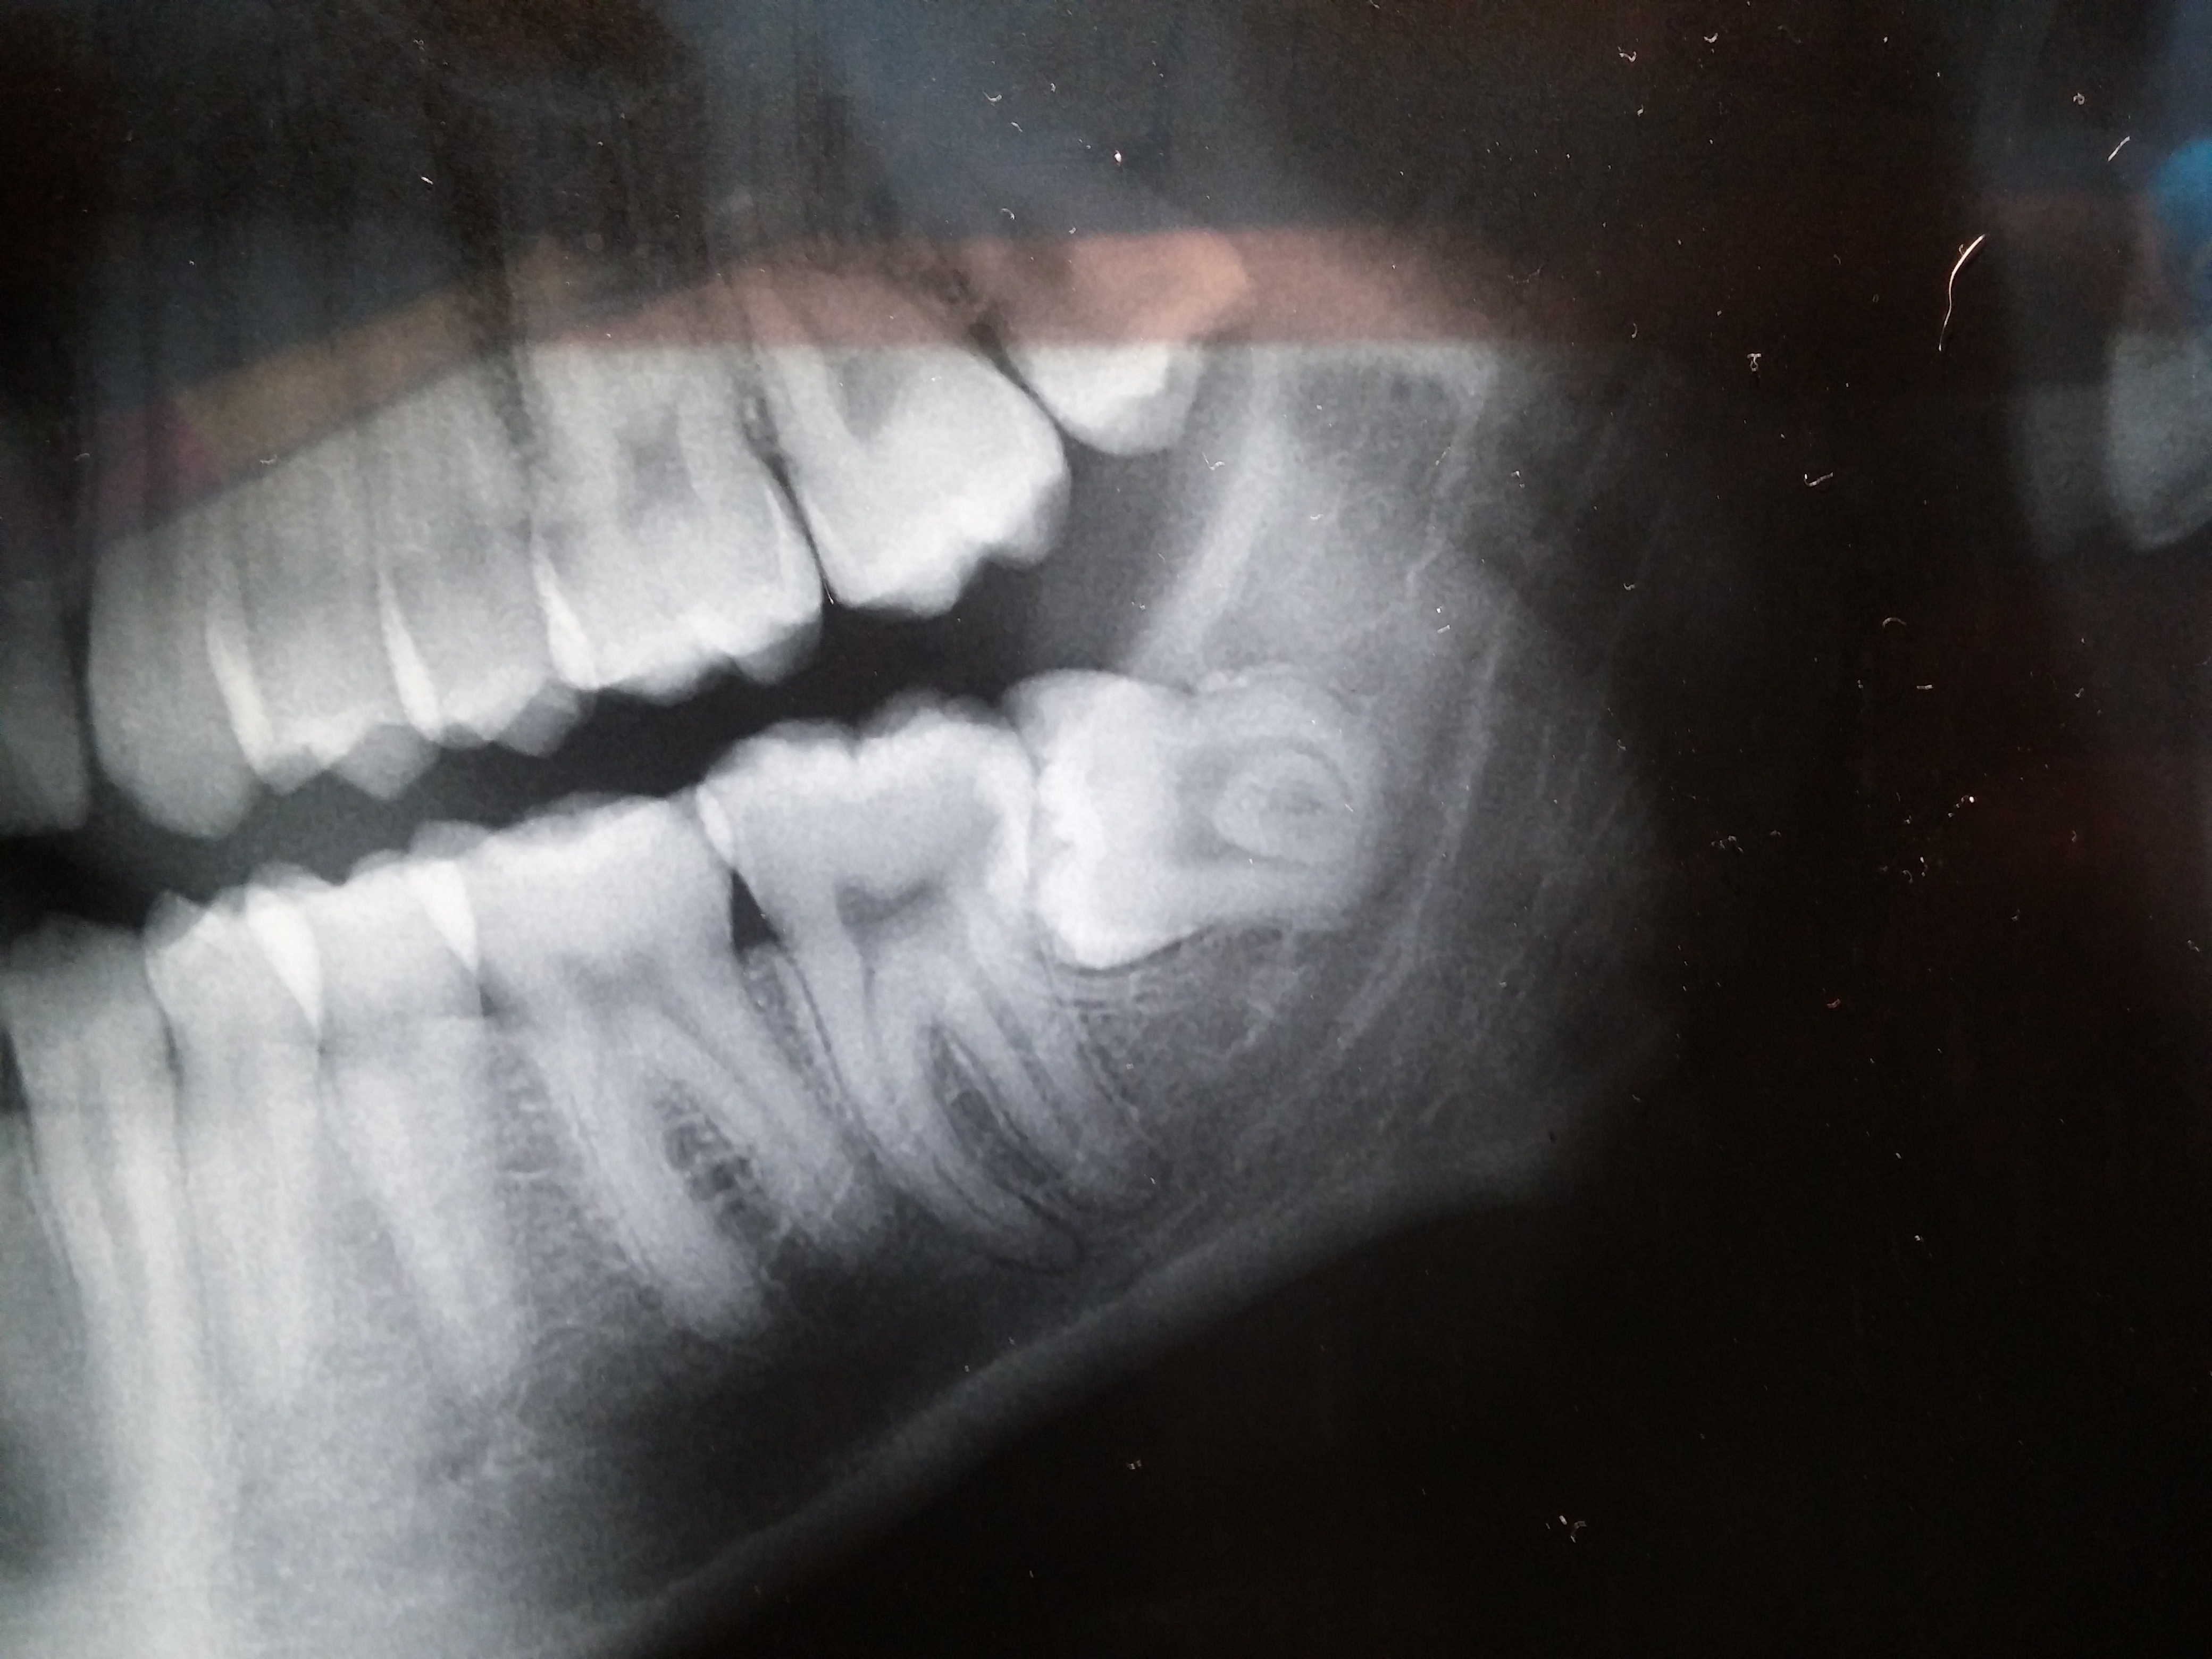

Denti del giudizio | Domande Pag. 23 (da 91 a 95)